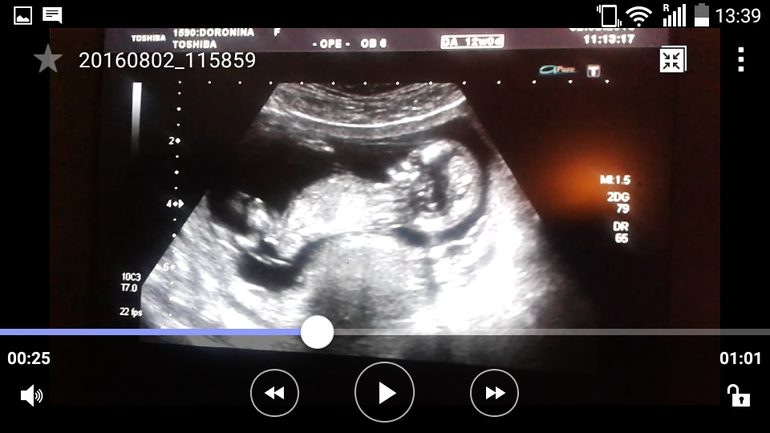

А что все ужи только снизу??? Может на видео есть боковой ракурс.

Вот моя доча вчера, поищите такой ракурс. У нас большой бугорок, но он параллельно позвоночника идёт.